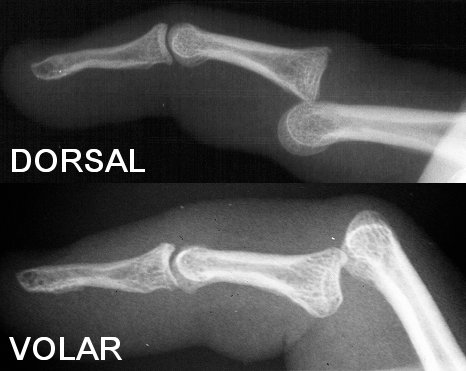

Figure Legend:

Proximal interphalangeal joint "simple" dislocations are usually

dorsal, and may be reduced by extending the finger to reproduce the

deformity and then dorsal pressure on the base of the middle phalanx.

These are usualy stable following reduction. Volar dislocations

represent a more serious injury, are less commonly easily reduced, and

more commonly unstable following reduction. Although often passed off

as a "jammed finger", PIP dislocations commonly result in 6-12 months

of swelling, PIP flexion contracture, and permanent joint enlargement.